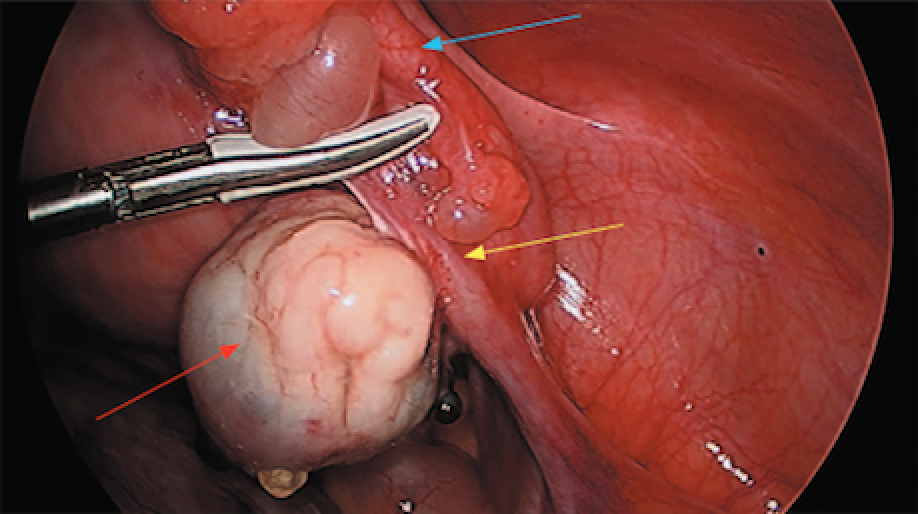

A 46-year-old male underwent a left laparoscopic radical nephrectomy for a cT1b renal cell carcinoma. Intra-operatively, a rent in the descending mesocolon was made during bowel mobilization but was not closed. Subsequently, the patient presented to the emergency room 4 days later with complaints of sudden onset sharp abdominal pain and nausea. A non-contrast computed tomography scan was obtained. What is the diagnosis?